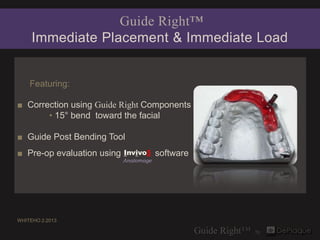

- 1. Guide Right™ Immediate Placement & Immediate Load Featuring: ■ Correction using Guide Right Components • 15° bend toward the facial ■ Guide Post Bending Tool ■ Pre-op evaluation using Invivo5 software Anatomage WHITEHO 2.2013